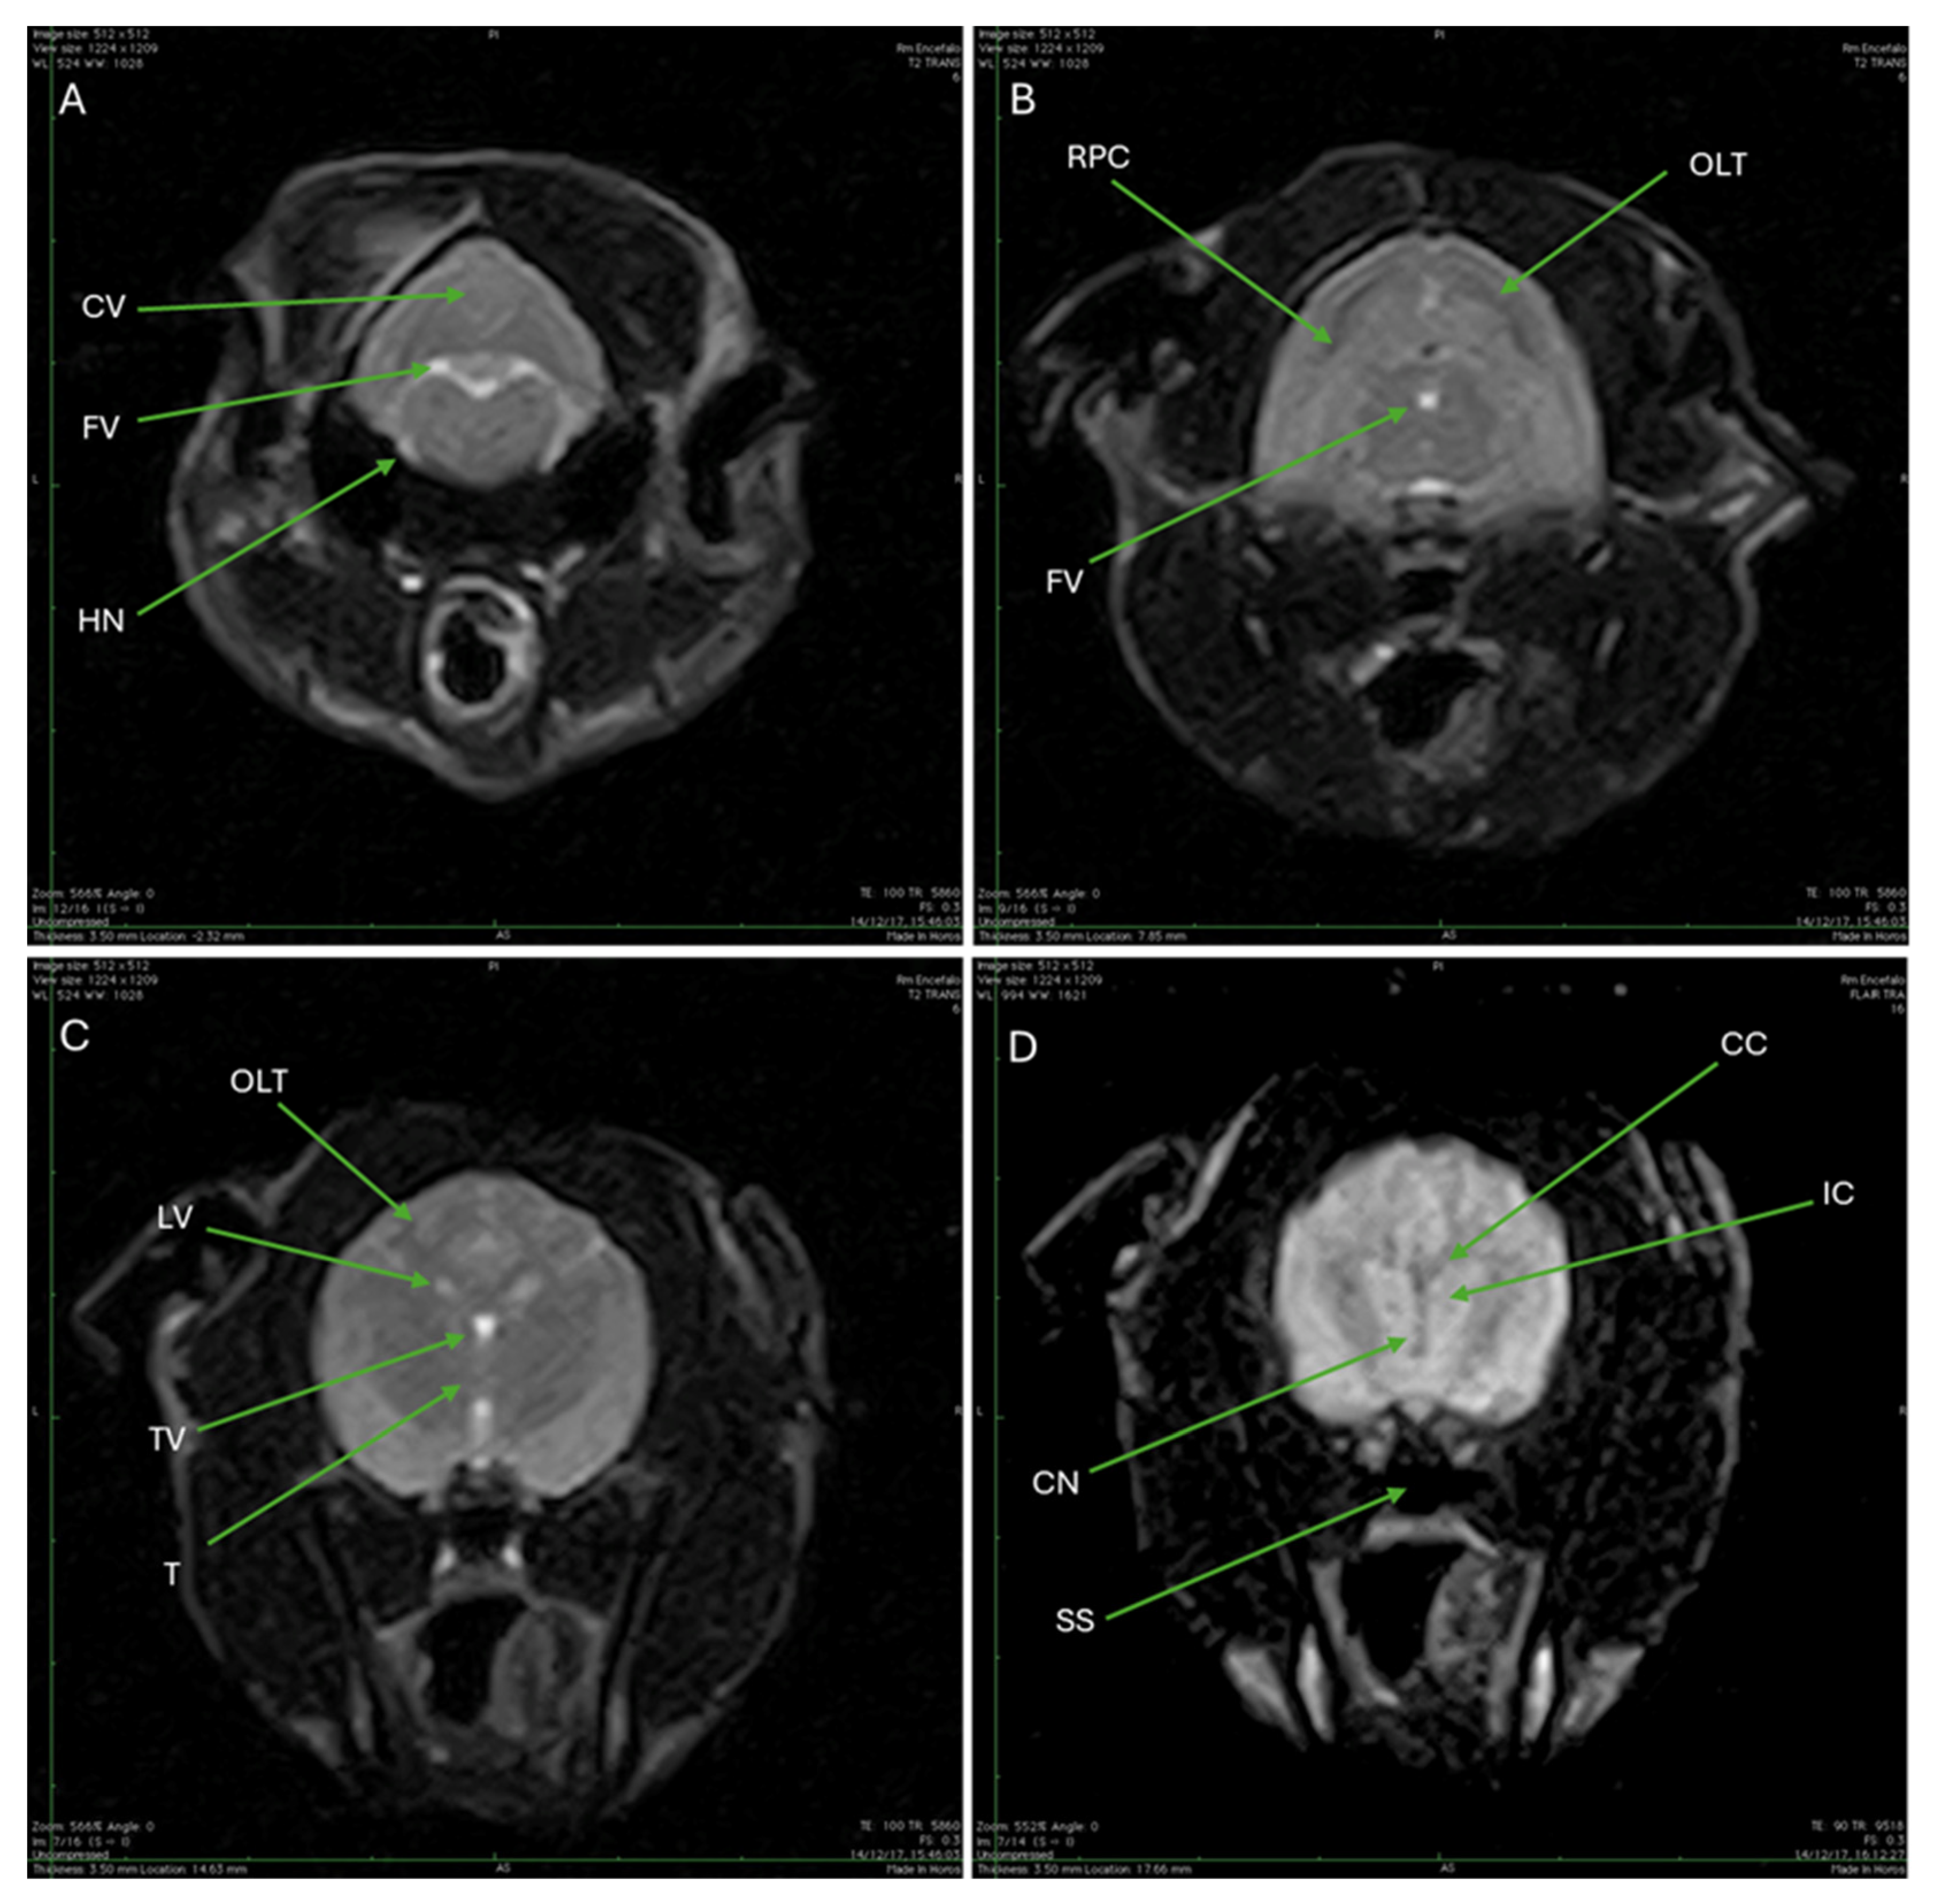

| CV | Cerebellar vermis |

| FV | Fourth ventricle |

| HN | Hypoglossal nerve |

| RPC | Rostral portion of the cerebellum |

| OLT | Occipital lobe of the telencephalon |

| LV | Lateral ventricles |

| TV | Third ventricle |

| T | Thalamus |

| CC | Corpus callosum |

| IC | Internal capsule |

| CN | Caudate nucleus |

| SS | Sphenoid sinus |

3.3. Magnetic Resonance Imaging (MRI)